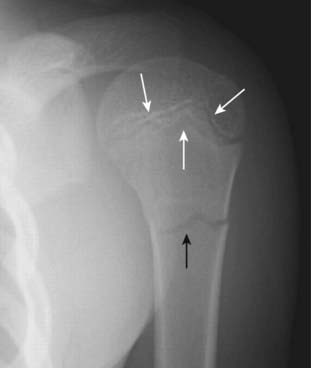

Figure 22-25 Scaphoid fracture.

Scaphoid fractures are common. They are suspected clinically if there is tenderness in the anatomic snuff box after a fall on an outstretched hand. Look for linear fracture lines on special angled views of the scaphoid (solid white arrow). Fractures across the waist of the scaphoid can lead to avascular necrosis of proximal pole of that bone.

Figure 22-26 Avascular necrosis of the proximal pole of the scaphoid.

A close-up frontal view of the wrist demonstrates that the proximal pole of the scaphoid (solid black arrow) is denser than the distal pole (solid white arrow). There is a fracture through the waist of the scaphoid (dotted white arrow). Because of the peculiar blood supply of the scaphoid (from distal to proximal), fractures through the waist may interrupt the proximal blood supply while the other bones of the wrist, having normal blood supply, become demineralized. This makes the proximal pole of the scaphoid appear denser relative to the other bones of the wrist.